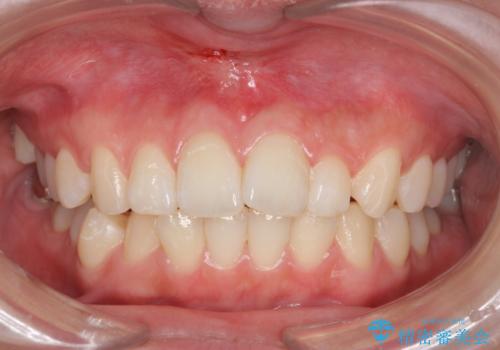

上唇小帯切除

担当医 青山卓弘